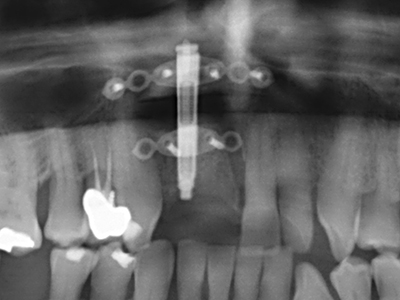

Como ya se ha demostrado en el pasado, básicamente cualquier procedimiento de cirugía de hueso representa una posible indicación para la cirugía piezoeléctrica. Así, la preparación del segmento móvil en la osteogénesis de distracción (fig. 23-25) y en la osteotomía de sándwich puede realizarse con piezas especiales, sin poner en peligro el suministro sanguíneo de la parte crestal, que resulta esencial para el éxito de ambas técnicas (González-García, Diniz-Freitas et al. 2008).

Para la extracción de implantes es posible realizar la preparación de una tapa ósea vestibular que, tras retirar el tornillo del implante, vuelve a fijarse y, de este modo, mantiene el contorno de la apófisis alveolar.

En la cirugía del seno maxilar surgen otros campos de aplicación: En este punto, tras la preparación concéntrica de una tapa ósea de la pared del seno maxilar (que suele tener forma trapezoidal), es posible eliminar patologías y cuerpos extraños del seno maxilar. La tapa ósea se repone después de finalizar la parte intra-antral de la operación y se asegura frente a una posible dislocación mediante cuñas o suturas adaptables.